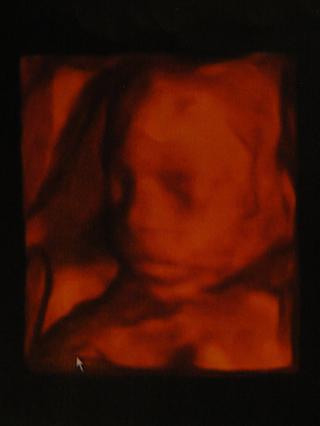

Jinak jsme dnes byli i na 3D - jak říkají doktoři, tak na show pro rodiče a bylo to hezký! Bylo zvláštní to mrně vidět v "reálné" podobě!🙂 Už máme 493g, takže teď by jsme to měli snad zvládnout i v případě nějakého problému!!! Podle paní doktorky jsme už v první polvině 23tt, ale radši se tím řídit nebudu! Tak tady Vám ještě toho našeho Marečka ukážu a jdeme do hajan!

Natalka...krásná fotečka 🙂 už se na tu show pro rodiče moooc těším.máš jen fotečku nebo i dvd?my jsme se s manžou domluvili,že fotečky nám budou stačit.Lukza:Je už Lukáškovi líp?

Máme i DVD! Nejdřív jsem si říkala, že taky postačí jen DVD, ale nakonec manža řek, že to bude taková památka i pro Marečka, až bude větší! Je tam hezky vidět, jak je akční, jak se mrská, jak otvírá pusinka, dává si nožičky k nosu atd.🙂 No však uvidíte...

Natalko, na Slovensku by si sa musela dnes poriadne napapať, aby Marečka vôbec zachraňovali... Tu sa zachraňuje podľa zákona až od 500 gramov.. ale to ten Tvoj dobehne tipujem niekedy dnes na obed... 😀 Pekná drobček, len je sranda, že ten Tvoj synček má úplne inú farbu pleti než môj... ja mám oranžového... 😀

Holky, ta barva je taková proto, že nemám skener a je přefocená na foťák, ale udělá to jinou barvu. Když to fotím do mobilu, tak je to úplně šedo-černé!!!🙂